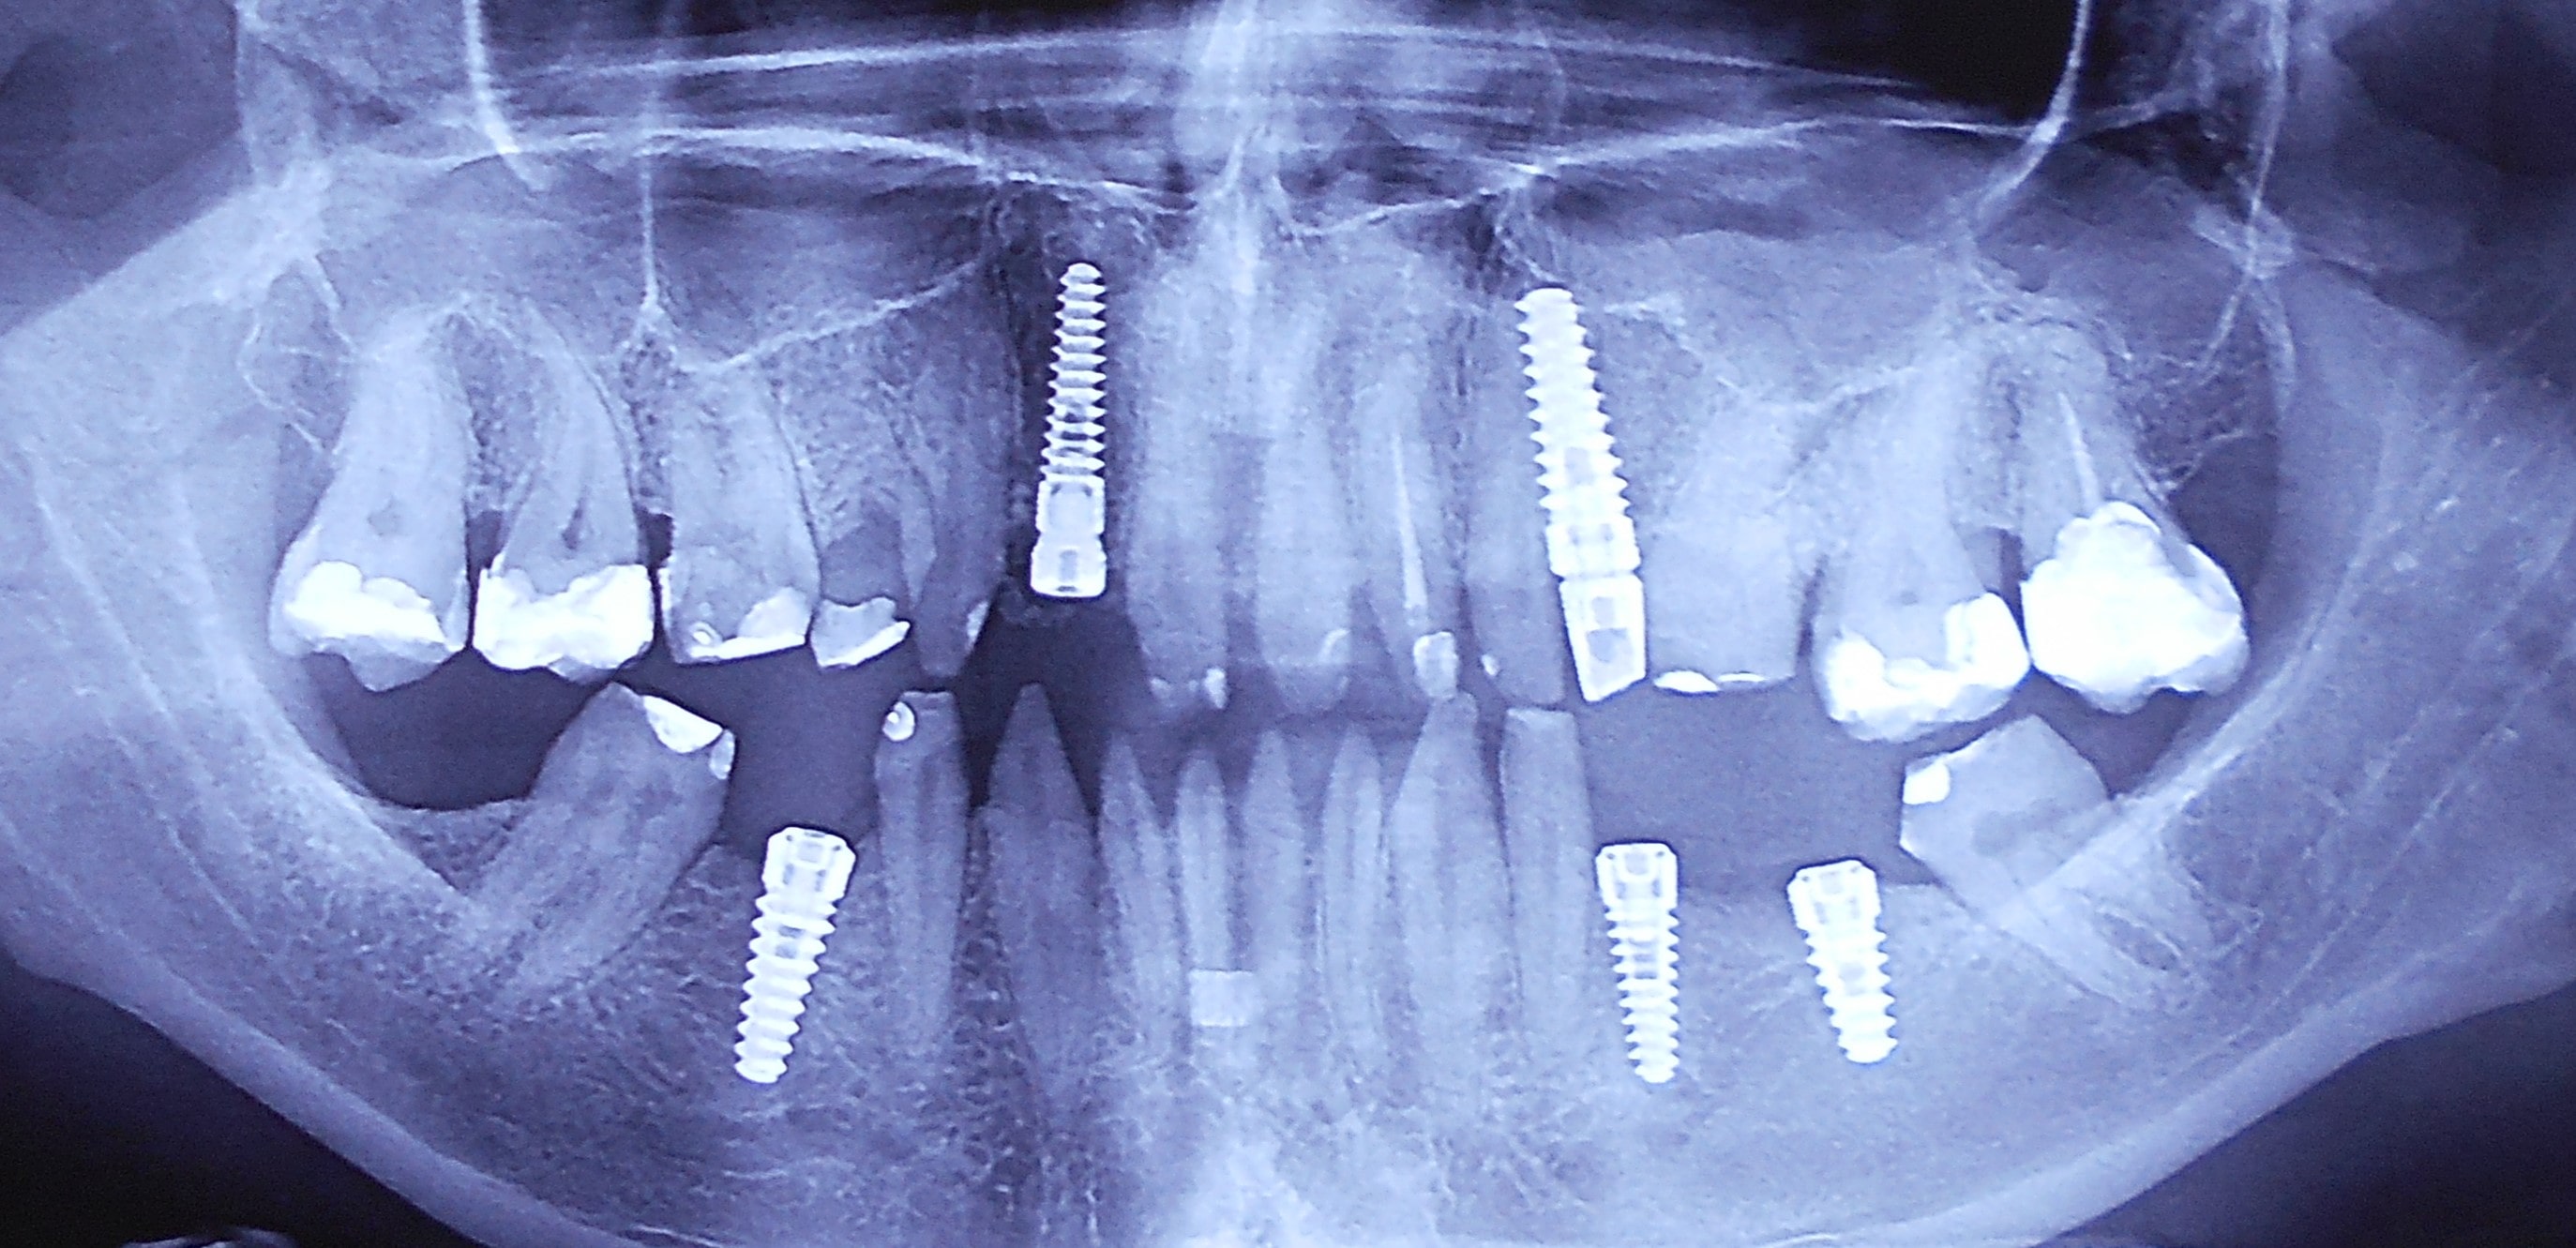

Pacijent iz inostranstva doalzi sa totalnom protezom u gornjoj vilici i sa uznapredovalom parodontopatijom preostalih zuba u donjoj vilici. Pacijent navodi da su mu u inostranstvu rekli da je nemoguće u gornjoj vilici ugraditi implantate bez velikih hirurških zahvata koji podrazumevaju transplantaciju kosti sa udaljenih delova tela i sinus lift proceduru. U gronjoj vilici je bila minimalna količina kosti sa izraženo spuštenim sinusima i sa minimalno vretikalnom i horizontalnom visinom kosti. Naše rešenje se sastojalo u sledećem: ugradnja deset implantata u gornjoj vilici u raspoloživu kost sa ugrdnjom veće količine veštačke kosti, od deset ugrađenih implanta dva implantata su tuberopterigoidna koji su zamenili sinus lift proceduru. U gornjoj vilici smo se opredelili za ugradnju većeg broja implantata kako bi prilikom izrade fiksnog protetskog rada dobili ravnomeran prenos pritiska žvakanja na implantate. U donjoj vilici intervencija je bila istovremena i ona je podrzumevala vađenje svih preostalih zuba i ugradnju osam implantata. Kompletno zbrinjavanje koje obuhvata hiruršku i protetsku fazu je trajalo tri meseca, tokom kojih je pacijent u gornjoj vilici bio zbrinut sa privremenom totalnom protezom, a u donjoj vilici sa fiksnim privremenim zubima koji su bili fiksirani na tek ugrađenim implantatima. Definitivni protetski rad je uspešno završen sa cirkonijum keramičkim - bezmetalnim mostovim pre četiri godine.